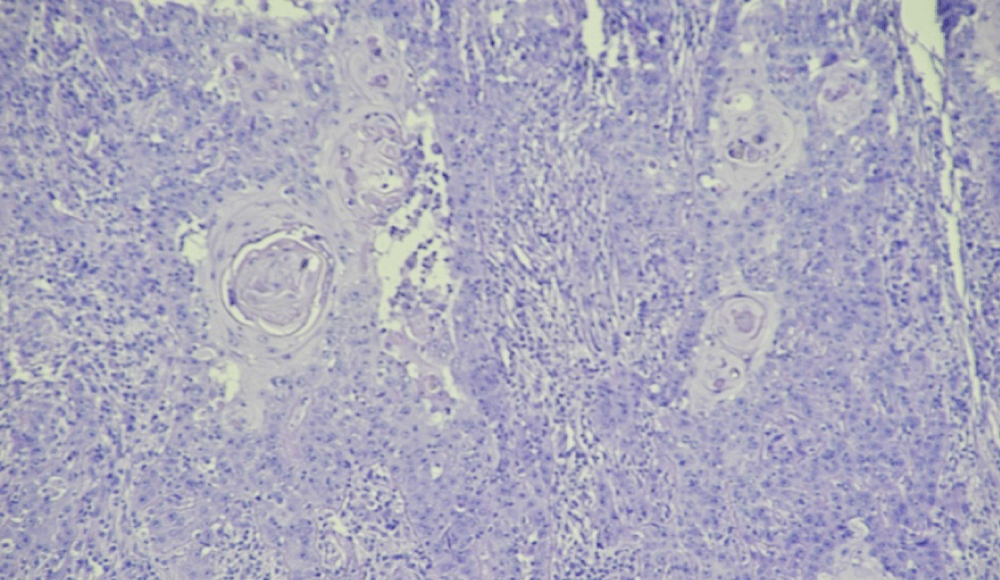

Marjolin’s ulcer developed on chronic radiodermatitis:A case report

El harrouni Alaoui A*, Elloudi S, Mrabat S, Douhi Z, Baybay H, Mernissi FZ

Marjolin’s ulcers are scar carcinomas most often arising in old burn injuries. They arise mostly in the extremities. We report a case of Marjolin ulcer type is a Poorly differentiated squamous cell carcinoma, developed on chronic radiodermatitis postauricular, of a 58-year-old male patient treated 7 years before for carcinoma of the parotid with radiotherapy.